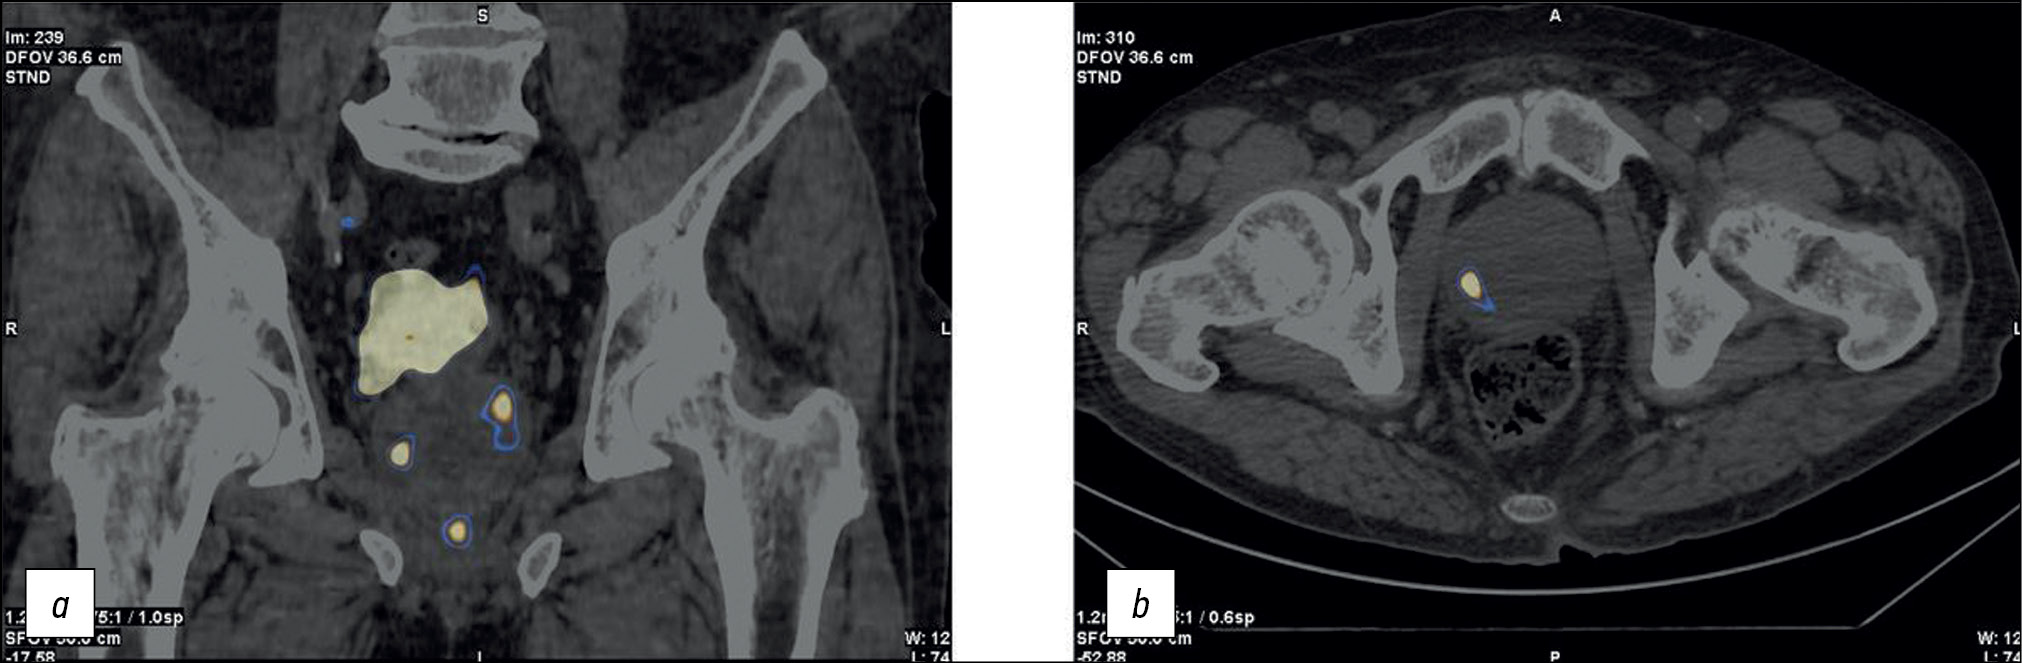

Patient M., 6 years old, had an increased PSA level of 6.8 ng/mL and underwent a multifocal prostate biopsy at a local clinic. The diagnosis was confirmed morphologically as adenocarcinoma, Gleason 6 (3 + 3), based on data from the transitory zone of the right prostate lobe. Adenocarcinoma elements were not found in other prostate biopsy specimens. Considering MRI evidence of changes in the same zone, implantation with 30 125I sources with a 32-cm3 volume was proposed.

SPECT/CT with 99mTc-HYNIC-PSMA revealed diffuse focal RP accumulation under the base of the bladder. PET/CT with 68Ga-PSMA-11 was additionally performed to more accurately visualize prostate lesions. PET/CT revealed multiple sites of RP accumulation in the prostate gland, indicating that the tumor was multifocal (Figure 8). Implantation planning was adjusted to include the total volume of the prostate gland (78 cm3) using 90 125I microsources (instead of preliminary 30 microsources).

Fig. 8. Patient M., 69 years old, PET/CT with 68Ga-PSMA-11: Sites of radiopharmaceutical accumulation in the prostate gland, multifocal tumor.

On February 25, 2022, implantation was performed for the total volume of the prostate gland. The initial prostate volume for brachytherapy was 32 cm3. PET/CT revealed a volume of 72 cm3 for implantation. The PSA level decreased to 0.31 ng/mL within a year after brachytherapy.